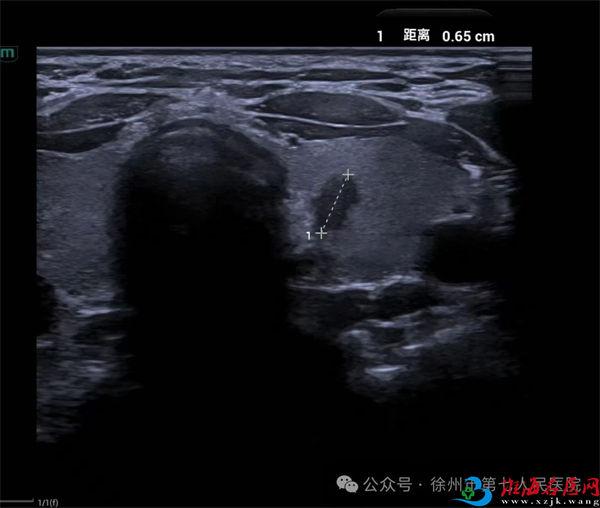

患者,女,30岁,在徐州市第七人民医院体检时发现甲状腺左叶多发结节,较大结节6×4×3㎜,纵横比>1,形态不规则,TR-RADS 4b。为进一步辨别结节的良恶性,拟行甲状腺细针穿刺,经综合评估,该患者适于FNA。

超声医学科主任殷志勇为患者进行超声引导下甲状腺结节细针穿刺活检术(FNA)。经超声引导,穿刺针精准进入病灶并取得了满意的标本。操作时间仅10分钟,整个术程顺利,患者无特殊不适。术后经病理科周新刚主任诊断,该例甲状腺结节的病理结果为可疑甲状腺乳头状癌(TBSRTC:V类)。